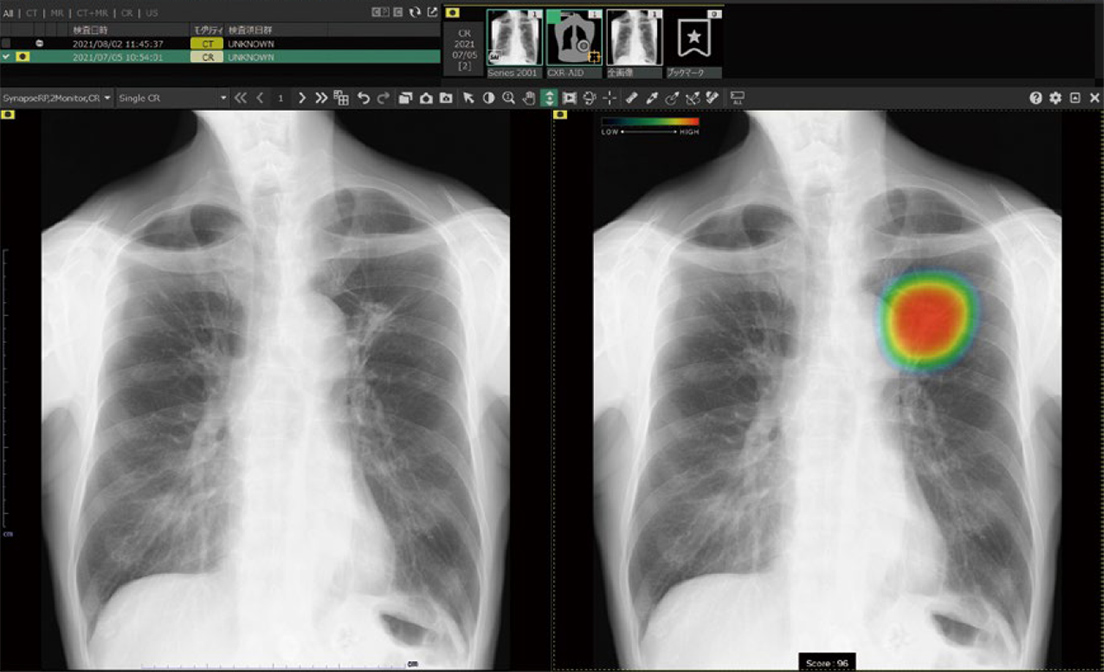

当院では、AI技術を用いて開発した、胸部X線画像病変検出ソフトウェアを導入しています。 AIが画像を解析することで病変を検出し、病気の早期発見に役立てるとともに、医師の診断をより確実なものにしています。 |

当院では、AI技術を用いて開発した、胸部X線画像病変検出ソフトウェアを導入しています。

AIが画像を解析することで病変を検出し、病気の早期発見に役立てるとともに、医師の診断をより確実なものにしています。